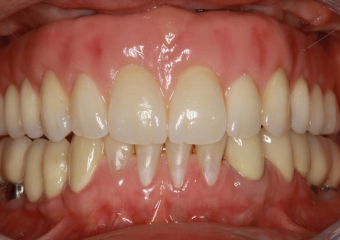

Prótese fixa em porcelana sobre implantes

Imagens da prótese fixa em porcelana e zircônia sobre implantes, do caso terminado em Fevereiro 2012